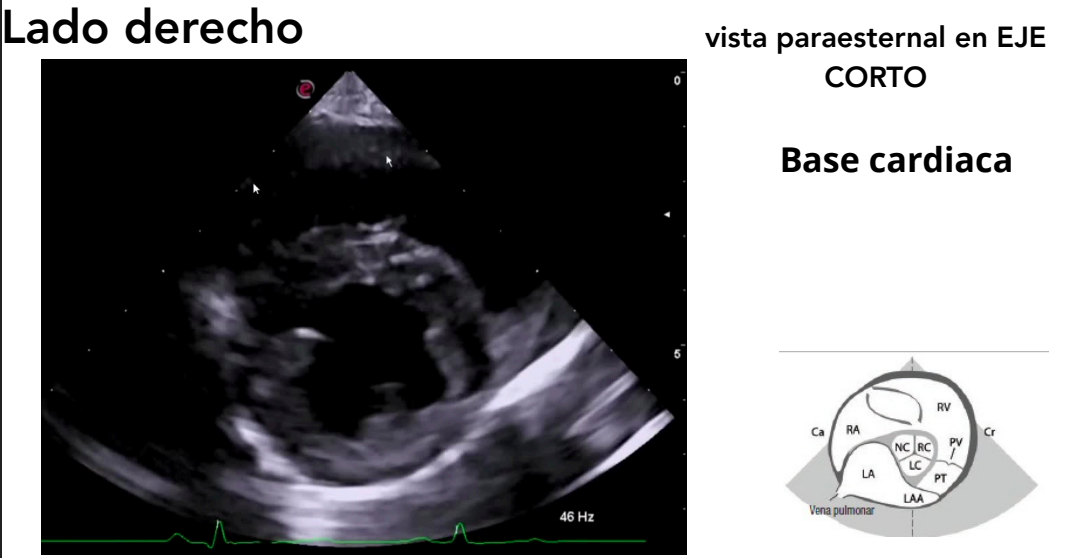

Vista paraesternal en eje corto

- Niveles observables:

- Músculos papilares ("champiñón")

- Válvula mitral ("boca de pez")

- Base cardíaca

- Tracto de salida del ventrículo derecho

Base cardiaca

Muy bueno para buscar mediciones, interesante para ver la dilatación del atrio izquierdo al compararlo con el de la aorta

El ratio atrio izquierdo/Aorta se mide con la vista paraesternal en eje corto de base cardiaca

Ratio AI/Ao

Relación entre el diámetro de la aurícula izquierda y la aorta.

Permite detectar dilatación auricular.

Valores superiores a 1.5–1.6 indican dilatación significativa.